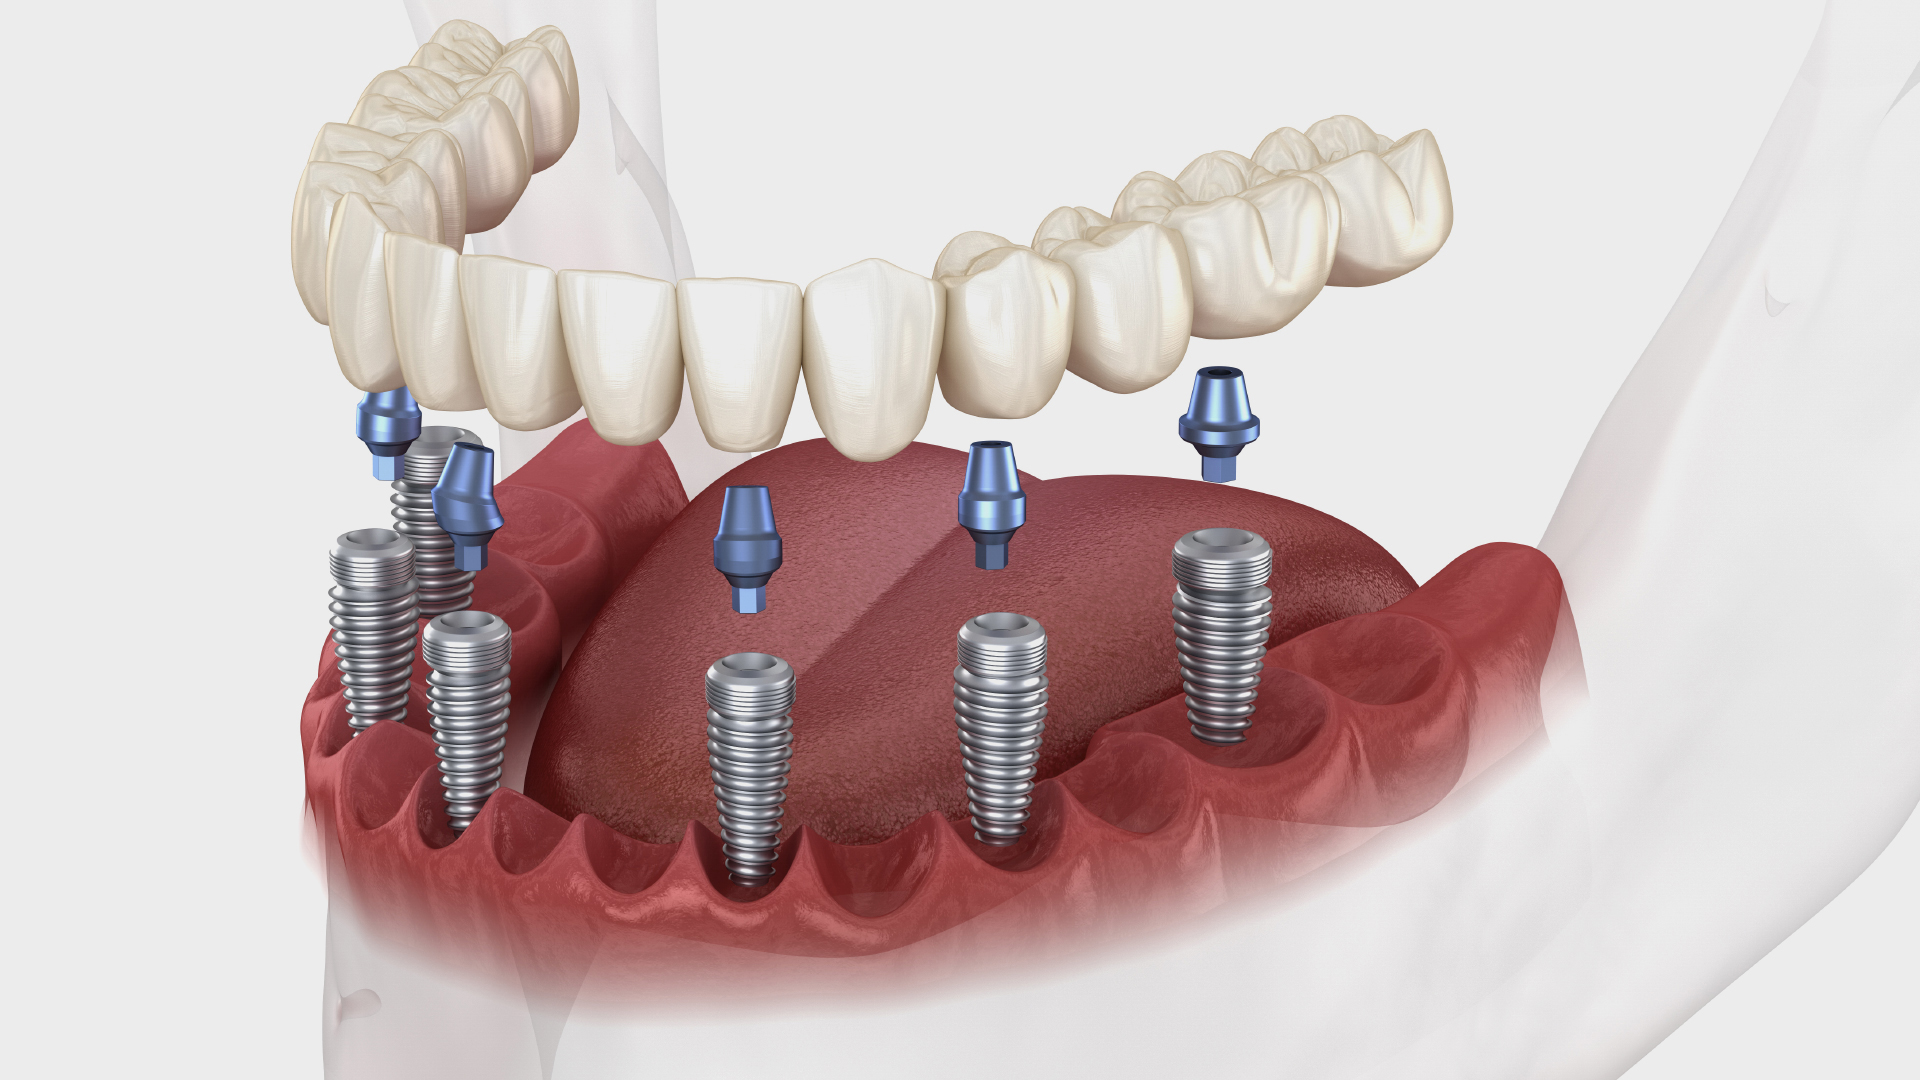

Dental implants are permanent, natural-looking replacements that restore function, aesthetics, and confidence in your smile.